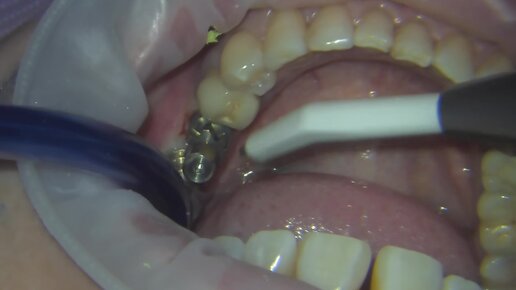

Снятие слепков с имплантатов

Стоматолог Краснодар Сорокин Михаил